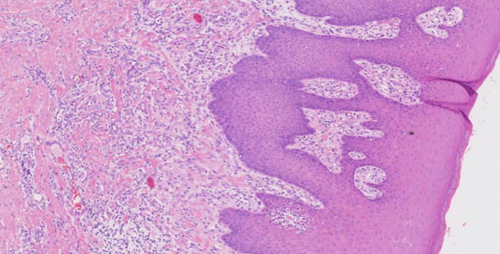

胃粘膜活检 低级别

胃粘膜活检  低级别至高级别上皮内瘤变

2023年04月01日 1394 03分52秒